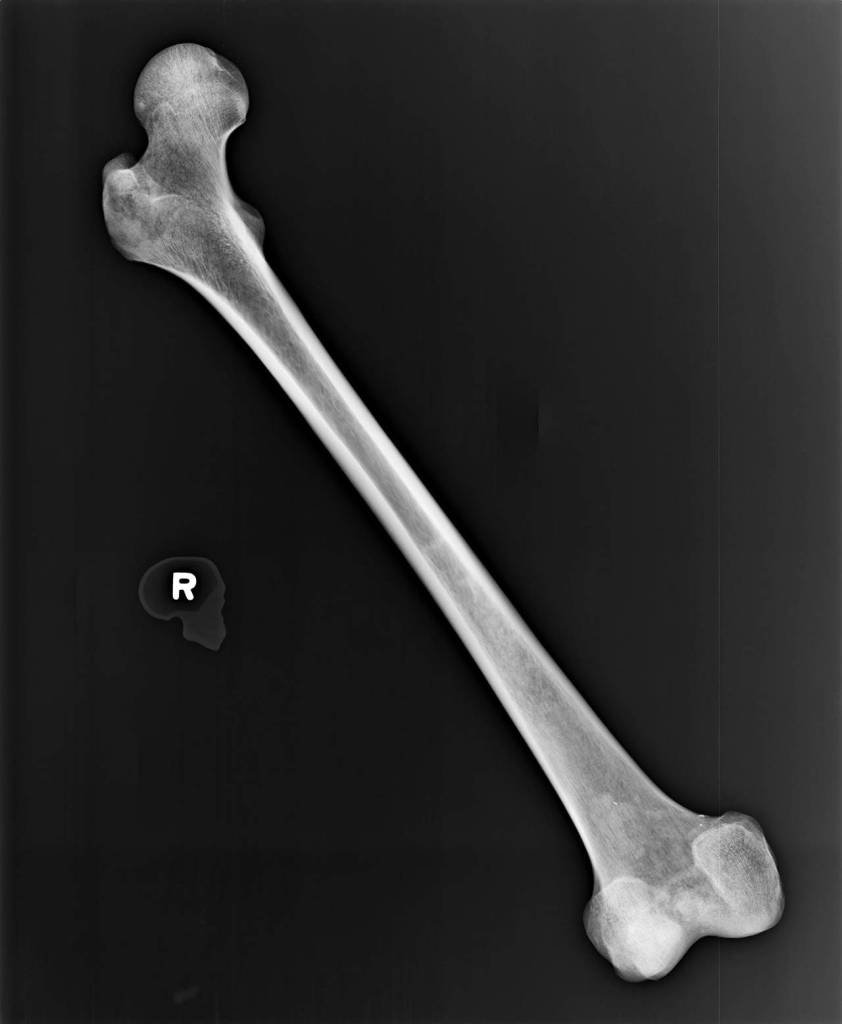

Picture a bone, the kind caricatured on a dog treat: smooth, straight and normal, with two knobs on each end. That’s a rough idea of the man’s right femur, the biggest and strongest bone in the body.

On his left side, he’d been living with a shattered thigh.

The X-ray shows the middle third of the bone stuck out like the claw of an ice scraper. We know he lived with it broken like that, because it healed, in a horrific way.

He would’ve stood two inches shorter on his left leg.

The break has telltale signs of a fracture that was never reset, according to the Snohomish County Medical Examiner’s Office. It grew worse over time.

Detectives believe he shuffled around on the injury for years, perhaps. There’s little doubt that he lived with chronic pain.

“We’ve never seen a fracture that healed like that,” Scharf said. “It’s almost like he was in a Third World country, or he just avoided medical help altogether.”